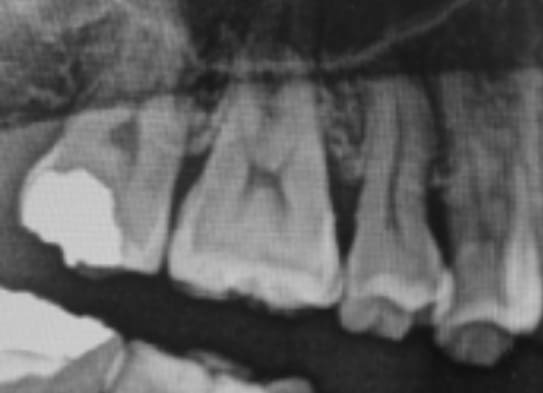

深いむし歯によって、歯髄が細菌に感染した歯

また、レントゲンで歯の根の組織まで細菌感染が及んでいないかを確認したり、実際の歯や歯茎の状態を目視で確認したり、患者さんから痛みの程度を聞いたりします。

むし歯が神経まで到達すると、歯の中の血管が炎症を起こし、ズキズキと痛みだします。

この場合は、炎症を起こした神経や血管を取り除く「抜髄(ばつずい)」が必要となります。

むし歯を放置したり外傷や歯周病によって神経が死んでしまった場合も、抜髄が必要です。